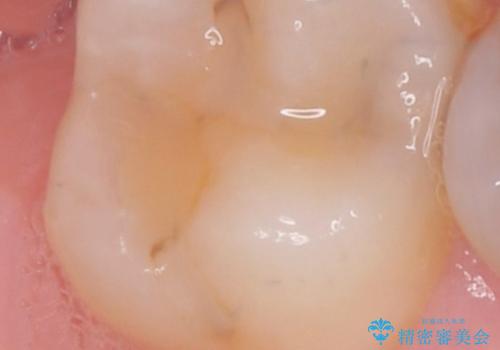

歯と歯の間の虫歯の治療。(コンタクトカリエス)

- メンテナンスで歯と歯の間に虫歯があったので拡大鏡下で虫歯を全て取り除き、e-maxインレーにて治療を行いました。